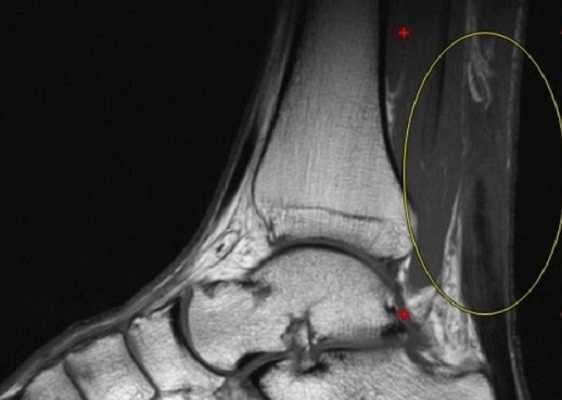

МРТ голеностопного сустава в корональной плоскости.

Отмечается поперечный стресс-перелом дистальных отделов малоберцовой кости.

МРТ голеностопного сустава в сагиттальной плоскости. Отмечается полный разрыв пяточного сухожилия с признаками повреждения паратенона, реактивного паратендинита.